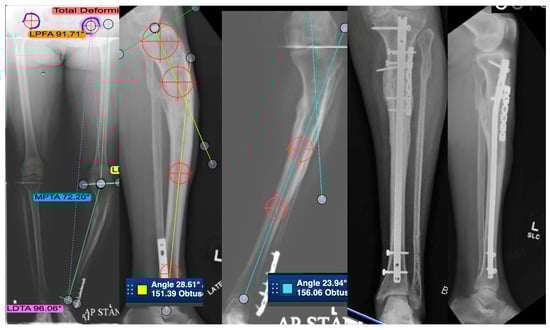

3.4. Distal Tibial Malunion

3.4.1. Demographics and Complications

3.4.2. Patients, Surgical Fixation, and Outcomes